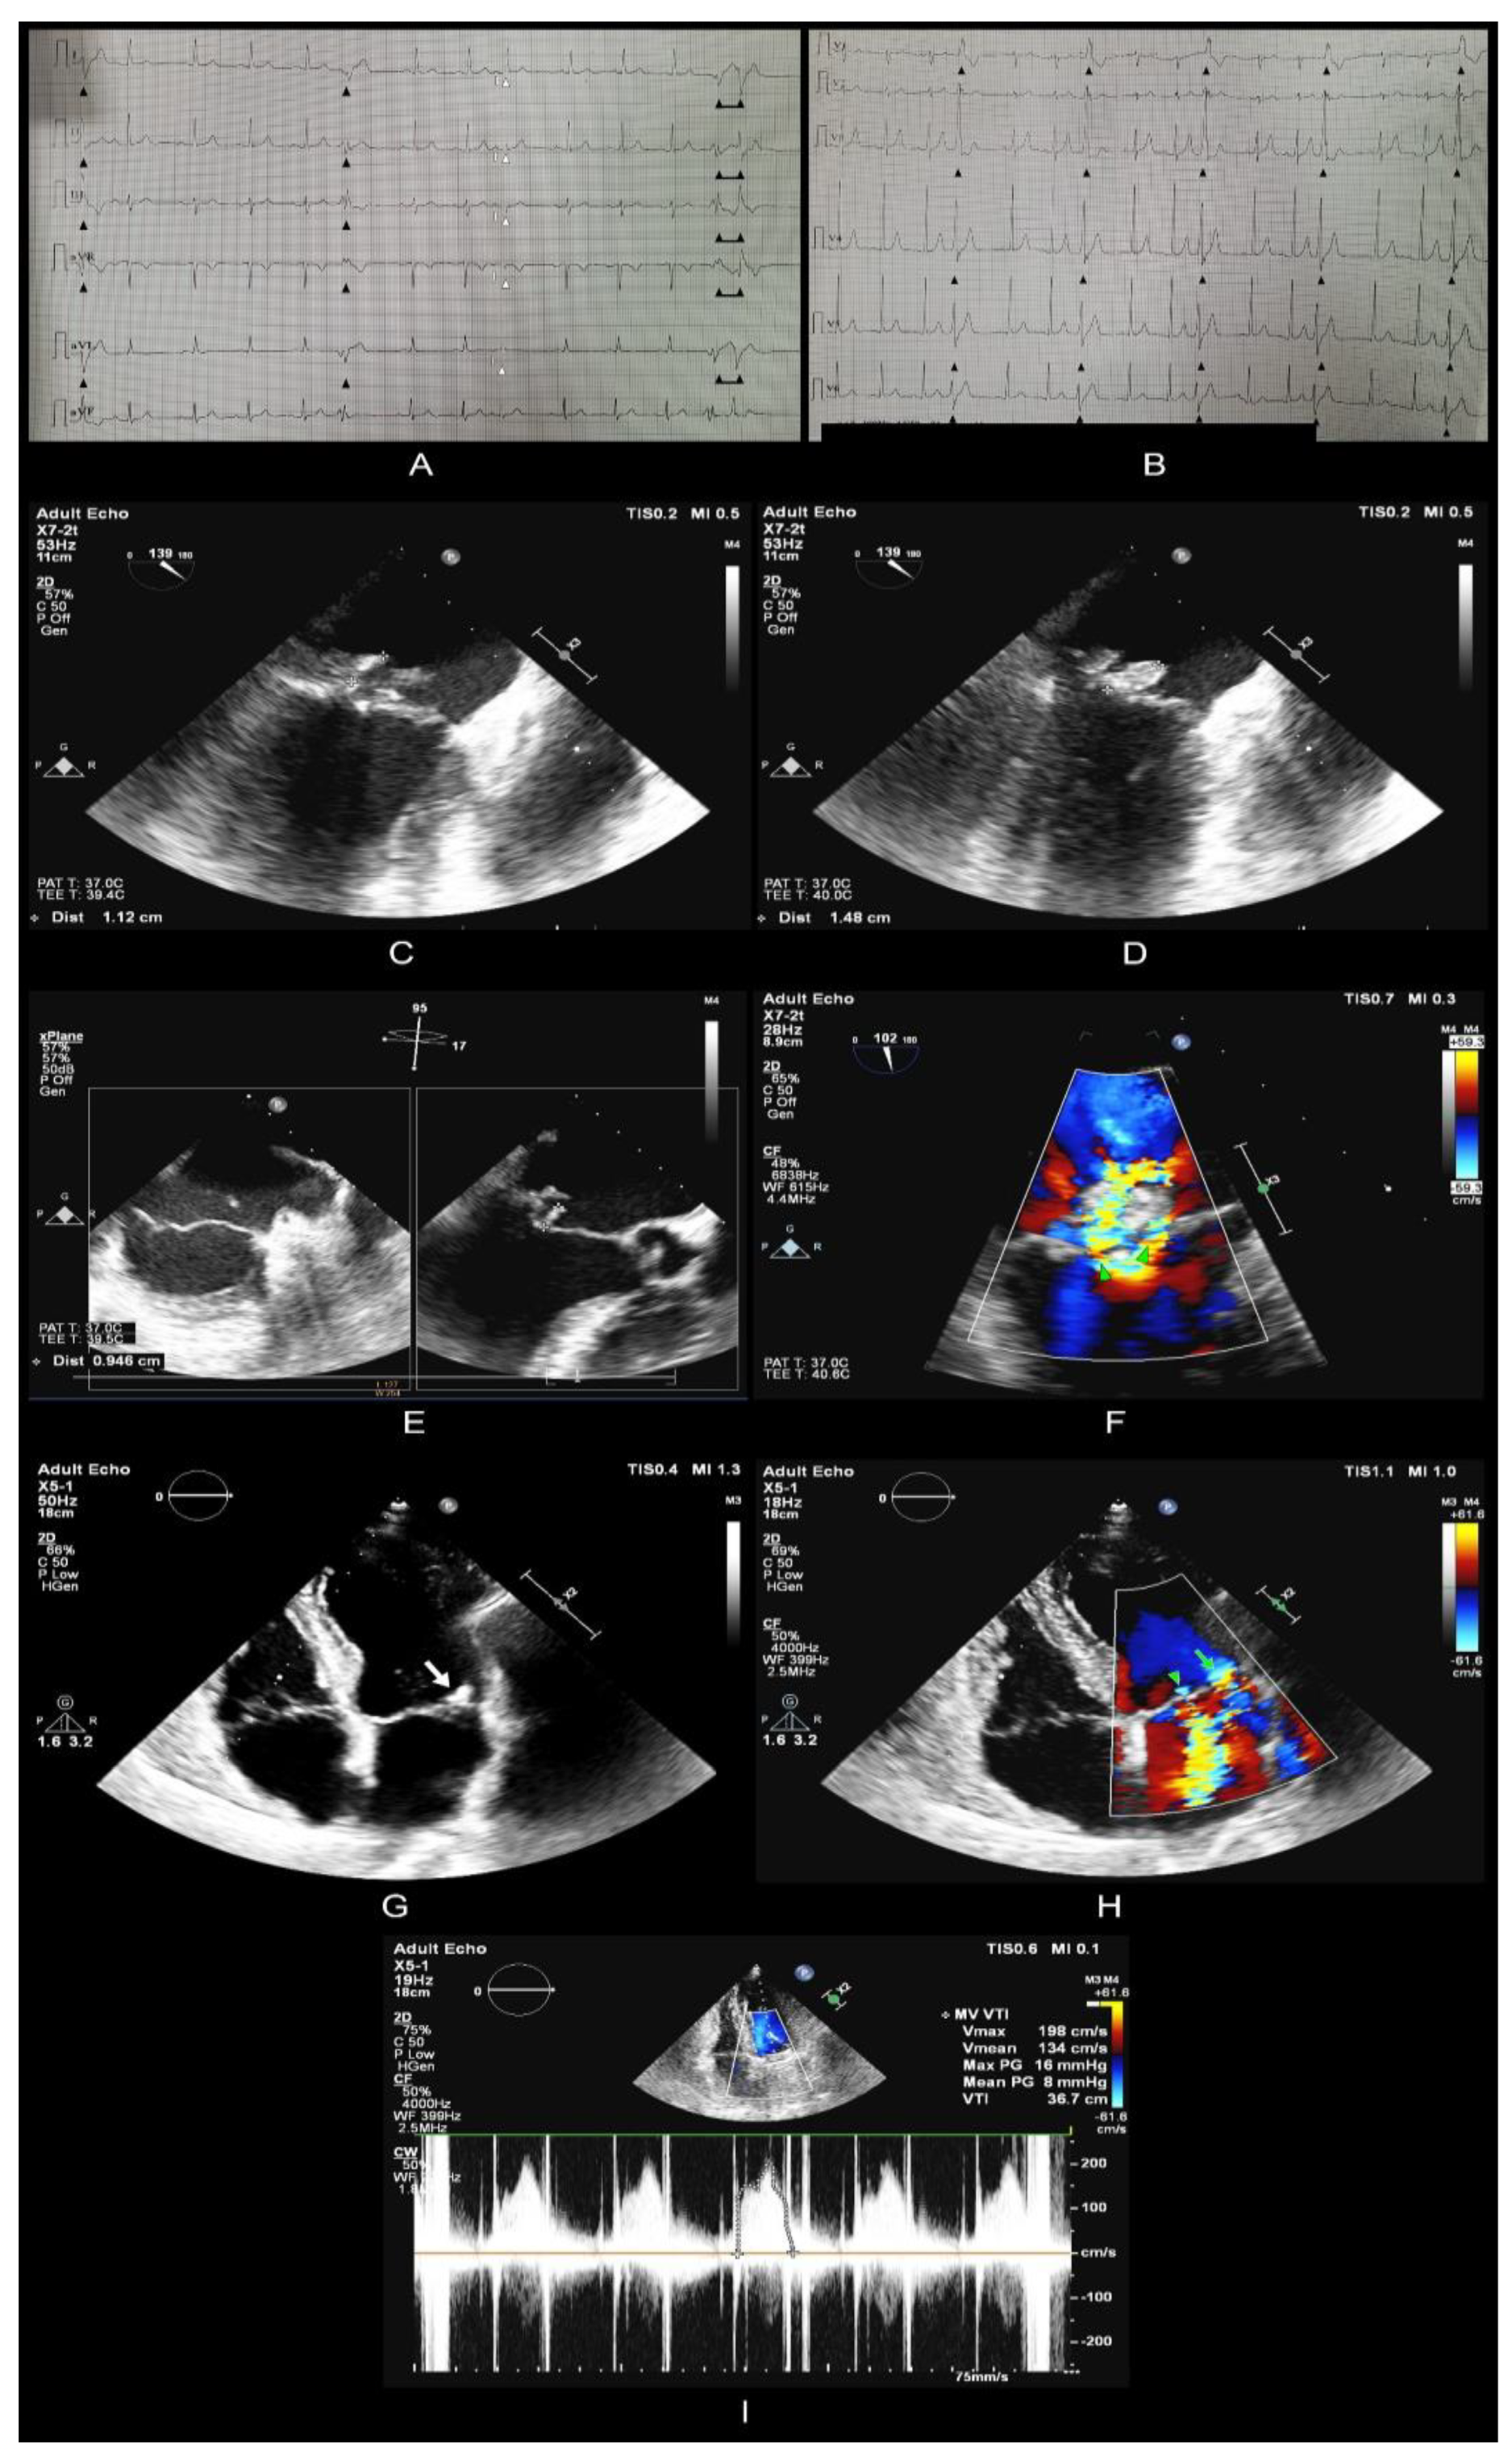

2. Case Report